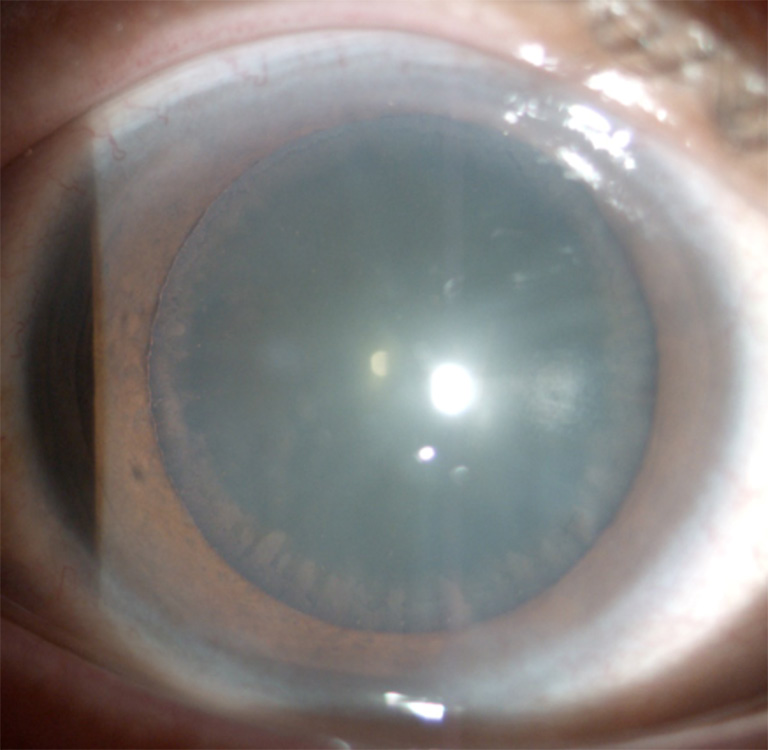

图2 病例1:散瞳后可见晶状体前囊周边部环状灰白色颗粒样混浊带

Figure 2 Case 1: deposits of white material as a granular peripheral zone on the anterior lens surface after pupillary dilation

患者,男,60岁,因右眼胀痛伴视力下降4个月,于西安市第四医院眼科就诊。眼部检查:右眼视力0.5,左眼视力0.8,右眼眼压50.3 mmHg(1 mmHg=0.133 kPa),左眼眼压14.6 mmHg。右眼结膜轻度充血,角膜未见水肿,角膜后沉着物(-),前房深度正常,房水闪辉(+),虹膜纹理清晰,瞳孔圆,直径约4 mm,对光反射迟钝,瞳孔缘可见灰白色碎屑样物质沉积(图 1),晶状体轻度混浊,散大瞳孔后可见晶状体前囊周边部环状灰白色颗粒混浊带(图 2),眼底视盘边界清,色淡白,杯盘比(C/D)约0.8,视网膜平伏,黄斑中心凹反光不清。左眼检查未见明显异常。患者既往体健。房角镜检查:双眼宽角,右眼房角可见较多大小不等色素颗粒沉着,跨越Schwalbe线,形成Sampaolesi线,色素III级,左眼色素I~II级(图 3)。Humphrey视野:右眼管状视野,左眼未见异常(图 4)。光学相干断层扫描(optical coherence tomography,OCT)检查:右眼视盘周围视网膜视神经纤维层厚度明显变薄(图 5)。诊断:1 )右眼剥脱性青光眼,2 )双眼年龄相关性白内障。给予右眼溴莫尼定滴眼液3次/ d、布林佐胺滴眼液3次/ d、噻吗洛尔滴眼液2次/ d联合甘露醇注射液静脉滴注降眼压治疗,完善术前检查排除手术禁忌证后,局部麻醉下行右眼复合式小梁切除术。术后第1天右眼视力0.4,眼压11.5 mmHg,上方结膜滤过泡隆起弥散,角膜透明,角膜后沉着物(-),前房中深,房水闪辉(+),瞳孔圆,直径4 mm,对光反射迟钝,瞳孔缘可见灰白色碎屑,虹膜周切口通畅,晶状体轻度混浊,眼底检查同前。术后1周右眼视力0.5,眼压15.8 mmHg;术后3个月,右眼视力0.5,眼压波动于15~18 mmHg,应用噻吗洛尔滴眼液,眼压波动于10~12 mmHg,滤过泡平坦,余检查大致同前。

XFG双眼发病时间和程度可以不对称,双眼发病者的年龄比单眼患者高,在所有单眼患者的对侧眼球结膜中均可发现剥脱样纤维物质存在。灰白色头皮屑样剥脱物质可沉积在瞳孔缘、晶状体前囊、角膜内皮、虹膜、前房角、睫状体带和玻璃体前界膜等处[6]。虹膜改变是本病早期易于发现的体征,32%~39%的患眼中可见到瞳孔缘头皮屑样剥脱物质沉着。晶状体前囊剥脱物质分布典型者表现为3个区域:1)中央盘(瞳孔区),为半透明绒毛状的中央盘形,出现率为80%,散瞳后尤为明显,可暴露盘形区的边缘部,呈薄片状;2 )中间透明带,位于中央盘形区与周边颗粒带之间,因剥脱物质被虹膜活动擦除而保持透明;3 )周边颗粒带,呈锯齿状或花边样灰白色颗粒样混浊环带,为本病的主要诊断依据。小梁网色素沉着增多早于瞳孔缘或晶状体前囊剥脱物质的出现。

本文报告的2例患者右眼瞳孔缘均可见典型灰白色碎屑样物质沉着,散瞳检查发现晶状体前囊周边颗粒带,房角镜检查小梁网广泛不均匀色素沉积,可见Sampaolesi线,患者眼压高,管状视野,故XFG诊断明确。治疗主要有药物、激光和手术。药物治疗同原发性开角型青光眼,但药物治疗效果相对较差[7]。散瞳可加重剥脱物质的数量及剥脱物质进入房角阻塞小梁网,所以慎用散瞳剂。氩激光小梁成形术早期降眼压效果理想,但术后炎症反应重,降眼压效果随时间逐渐下降,3~6年内降至35%~55%,远期效果较原发性开角型青光眼差。对于闭角型XFG患者,由于悬韧带异常晶状体前移,治疗上以摘除晶状体为主。XFG患者就诊时眼底及视野损害均较重,对降眼压药物反应差,病程进展快,多数患者需手术干预。本文2例患者就诊时已是晚期青光眼,眼压高,管状视野,因此选择手术治疗。